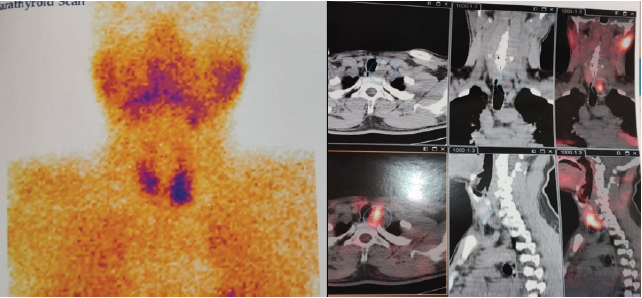

Subsequently, parathyroid scintigraphy was performed, revealing focal tracer uptake in hypodense foci posterior and inferior to the lower pole of the left lobe of the thyroid gland, measuring 20 × 17 × 25 mm (Fig. 3).

Figure 3: Parathyroid scintigraphy showing a hyperfunctioning parathyroid gland.

These findings were consistent with hyperfunctioning parathyroid adenoma involving the left inferior parathyroid gland, leading to the diagnosis of primary hyperparathyroidism. Both the endocrinologist and the head and neck surgeon consultations were done.